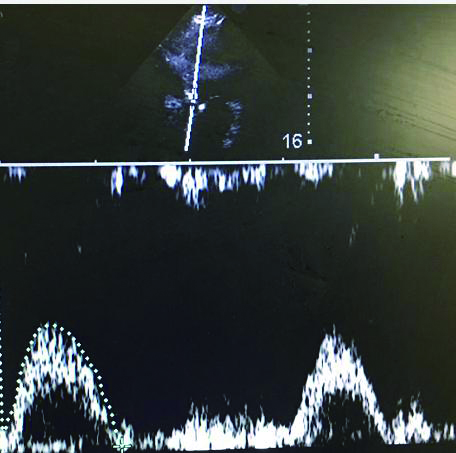

充分暴露前胸部,于胸骨旁长轴切面,选取主动脉瓣根部测量左室流出道直径与截面积。选取心尖五腔心切面,通过脉冲多普勒测量动脉流速,计算左心室流出道收缩高峰期的流速时间指数,测量心率,最后通过心脏检查软件包自动计算出CO(图 3、4)。通过上述PLR试验,联合超声获得的CO,最后计算ΔCO值,ΔCO≥15%定义为容量反应性阳性;反之为容量反应性阴性。

| 图 3 胸骨旁长轴主动脉根部 Figure 3 The aortic root at parasternal long axis |